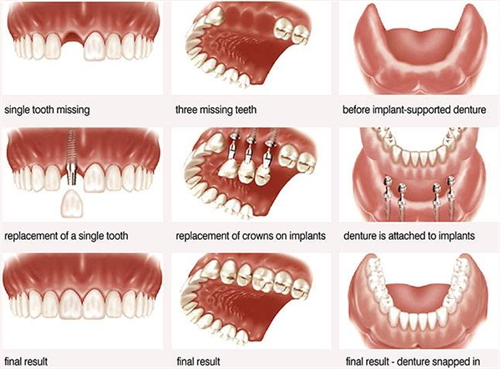

当糖尿病导致牙齿脱落时,患者可能会考虑补牙来修复口腔功能和美观。

然而,糖尿病患者的口腔健康情况较一般人更为复杂,补牙需要根据个体情况综合考虑。

在牙齿脱落的情况下,医生可能会建议进行种植牙或其他修复方式,但需注意糖尿病对口腔愈合和修复的影响。

3、糖尿病牙齿掉了一颗怎么处理

如果糖尿病患者的牙齿掉了一颗,应及时就诊寻求正规建议。

医生可能会进行口腔检查,评估口腔健康状况,然后制定相应的治疗方案。

在糖尿病患者的情况下,治疗过程可能需要更加细致和谨慎,以确保口腔修复的成功和长期结果。